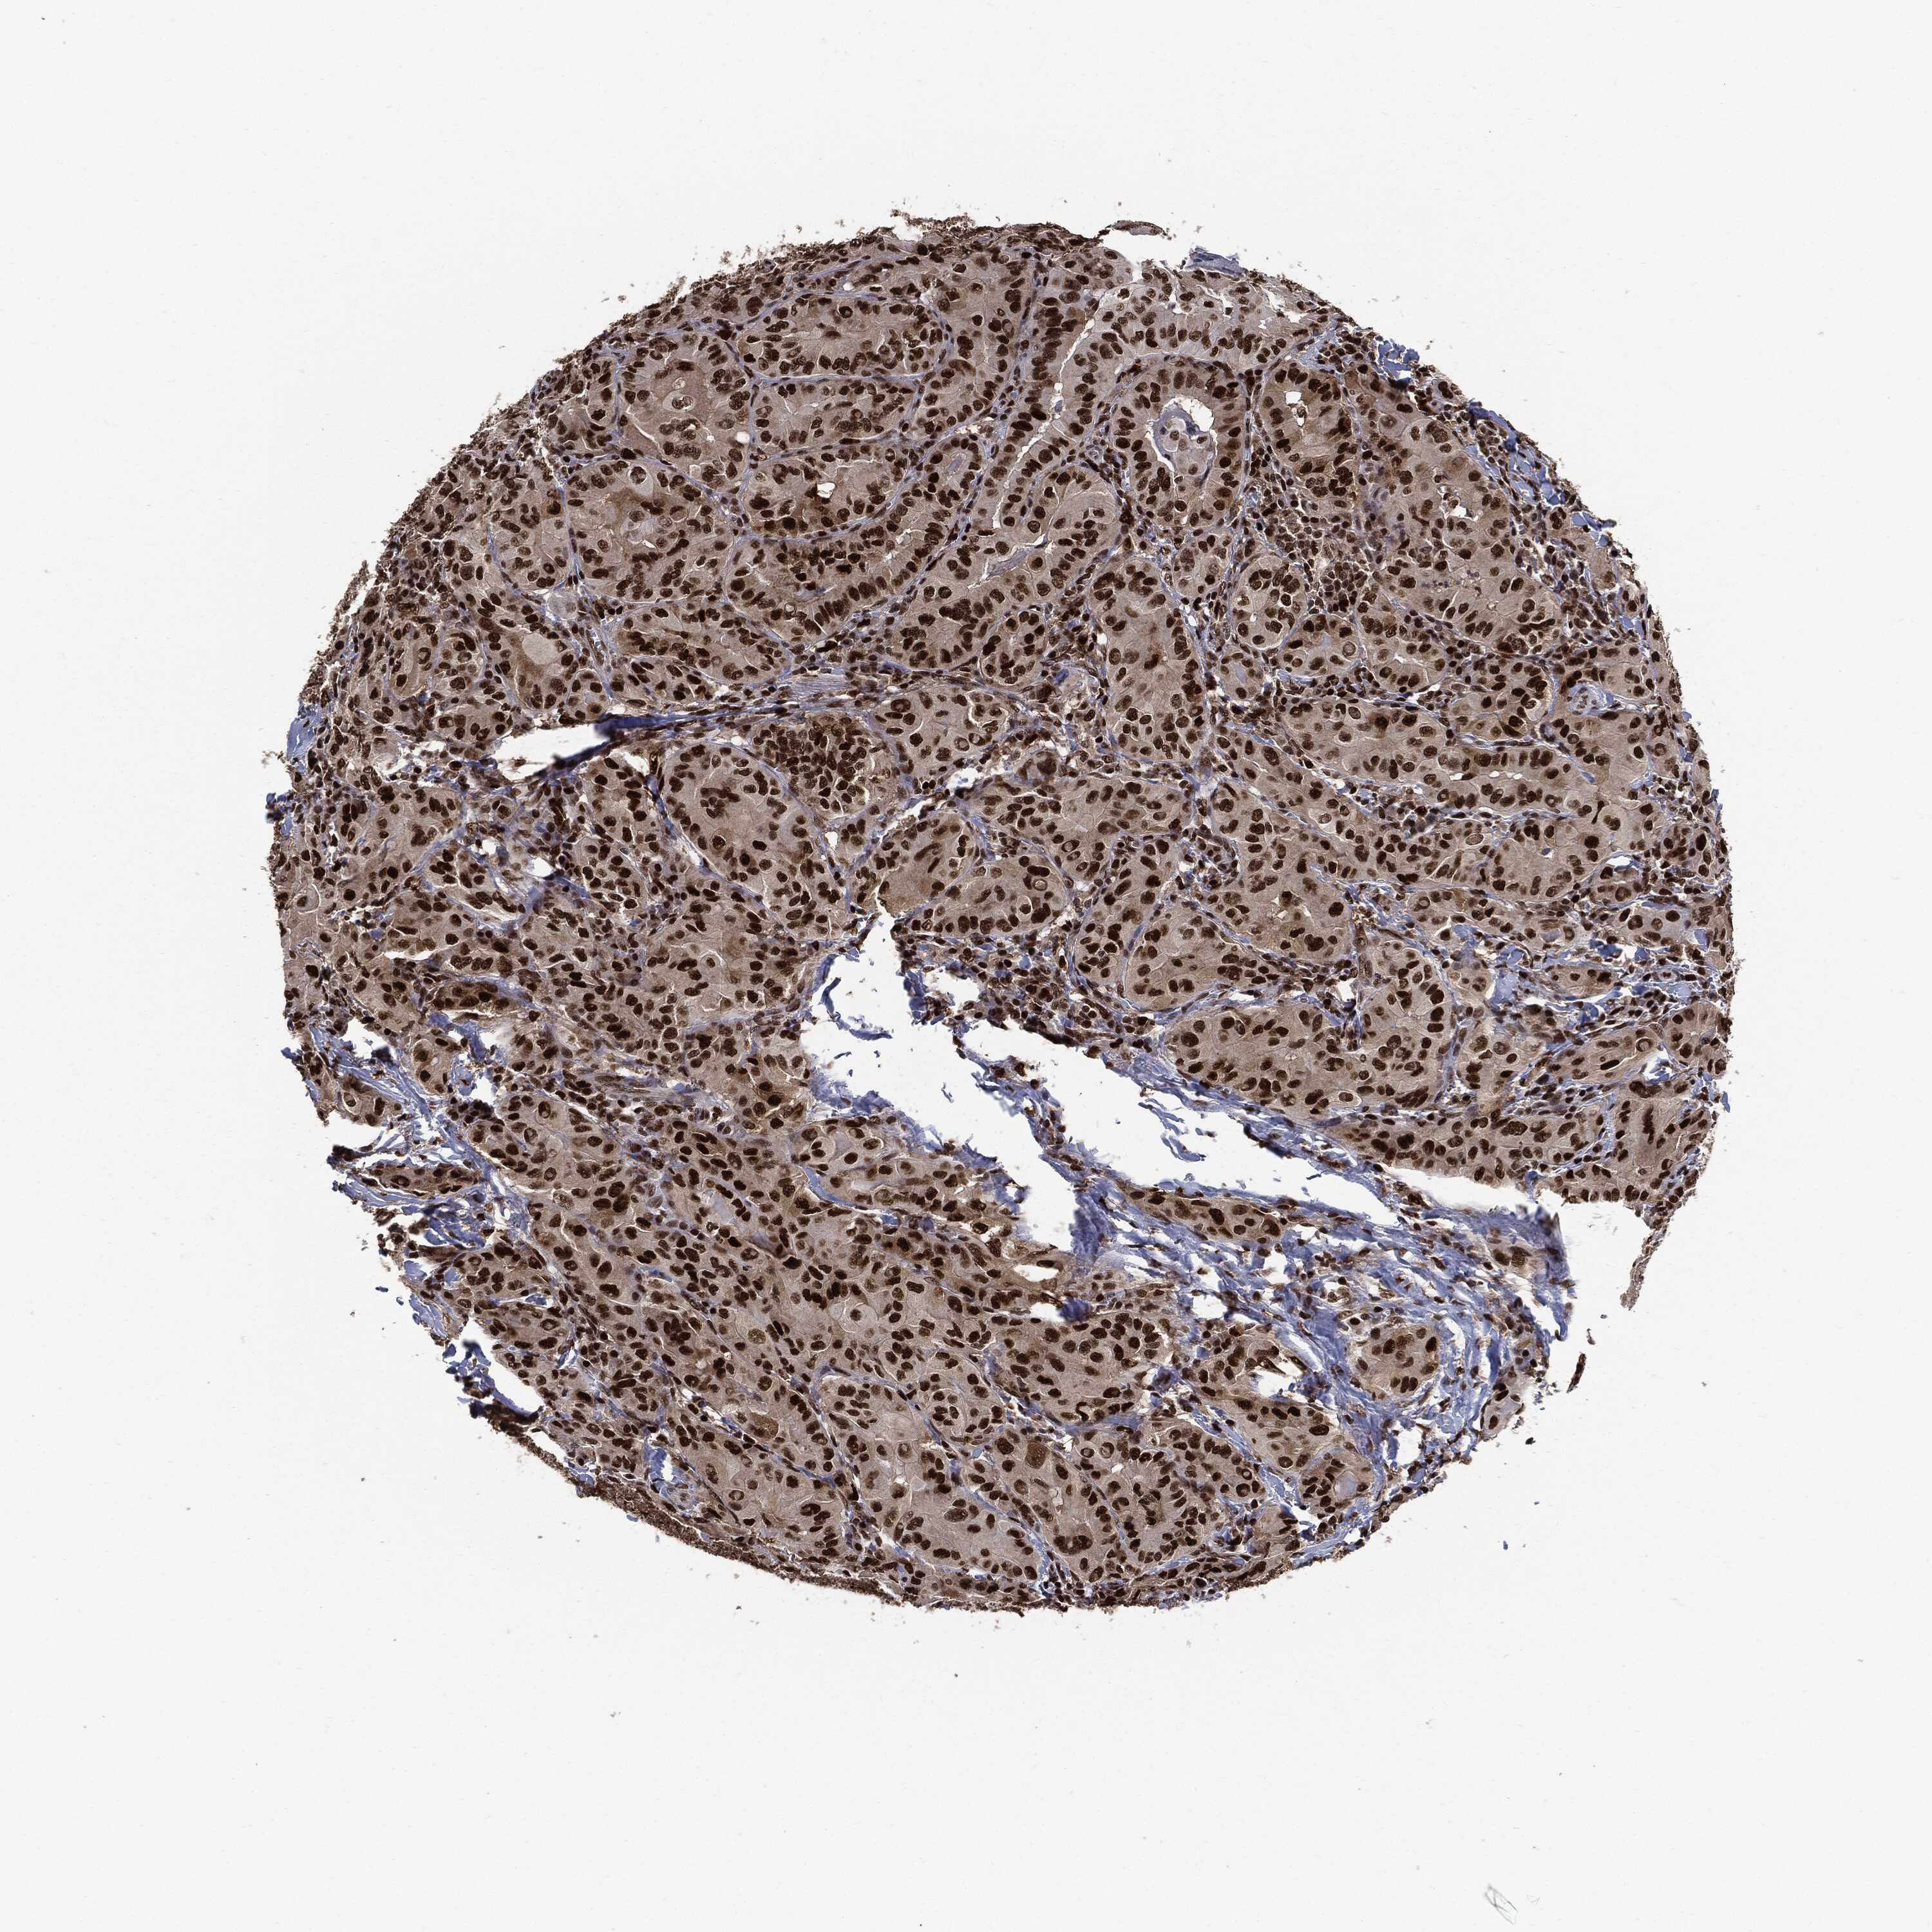

THYROID CANCER - Protein expressioni

A mouse-over function shows sample information and annotation data. Click on an image to view it in a full screen mode. Samples can be filtered based on level of antibody staining by selecting one or several of the following categories: high, medium, low and not detected. The assay and annotation is described here.

Note that samples used for immunohistochemistry by the Human Protein Atlas do not correspond to samples in the TCGA dataset.

Antibody stainingi

Antibody staining in the annotated cell types in the current human tissue is reported as not detected, low, medium, or high, based on conventional immunohistochemistry profiling in selected tissues. This score is based on the combination of the staining intensity and fraction of stained cells.

Each image is clickable and will lead to virtual microscopy that enables deeper exploration of all samples and also displays staining intensity scores, fraction scores and subcellular localization as well as patient and tissue information for each sample.

HPA030521

HPA030522

HPA030523

CAB000148

CAB080240

CAB080241

CAB080242

Staining

High

Medium

Low

Not detected

Intensity

Strong

Moderate

Weak

Negative

Quantity

>75%

75%-25%

<25%

None

Location

Nuclear

Cytoplasmic/membranous

Cytoplasmic/membranous,nuclear

Papillary adenocarcinoma, NOS

Follicular adenoma carcinoma, NOS

Carcinoma, NOS